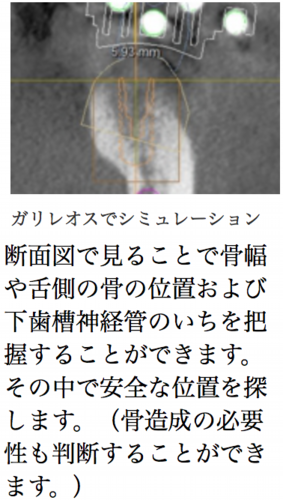

3Dカメラを使うセレックシステムとCTを3D解析できるガリレオスのデータを融合して、すべてコンピューターの中でインプラント埋入、アバットメントセット、かぶせのセットまでシミュレーションできてしまう、超先進技術です。まるで未来にきたように錯覚するかもしれません。これにより最終的な形が予測できる上、危険な治療ではないか、加えて必要な治療があるかどうかもわかります。

セレックとガリレオスを用いた本格的ガイドシステム

セレックガイドとは一般名称でいう、「サージカルガイド」のことであり、安全なインプラント治療のために、今までも世界レベルで使用を推奨されている重要なものであることは報道などでもご存知の方はいらっしゃるかと思います。ですが今までは海外にデータを送る必要もあり、その費用も高額のものでした。ですが、シロナ社はセレックガイドシステムという画期的なシステムをついに成功させました。「セレックガイド」は病院内で作成可能なため、安全がより身近にそして素早く制作することが可能になったのです。しかも従来よりも低価格で。